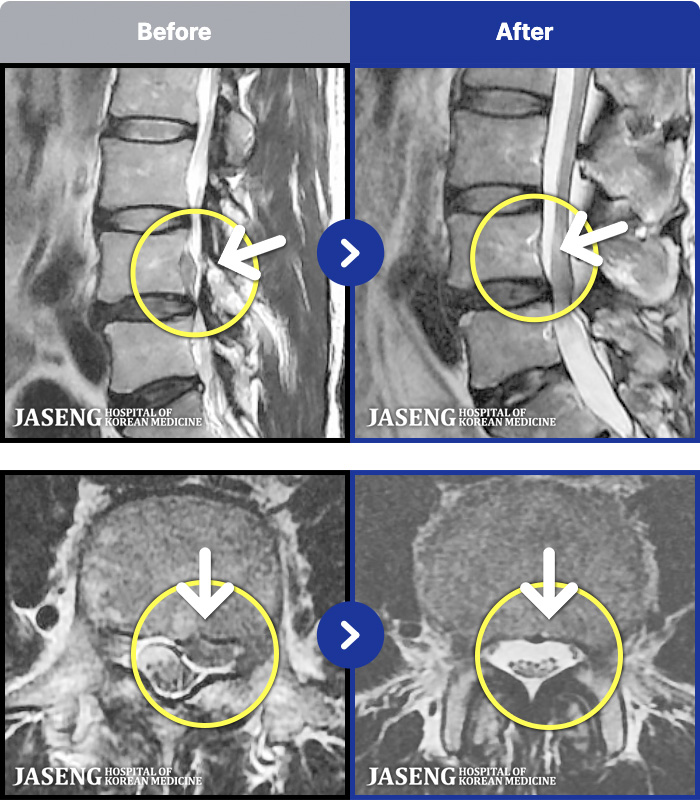

1,287 MRI ũ ʸ Ȯϼ.